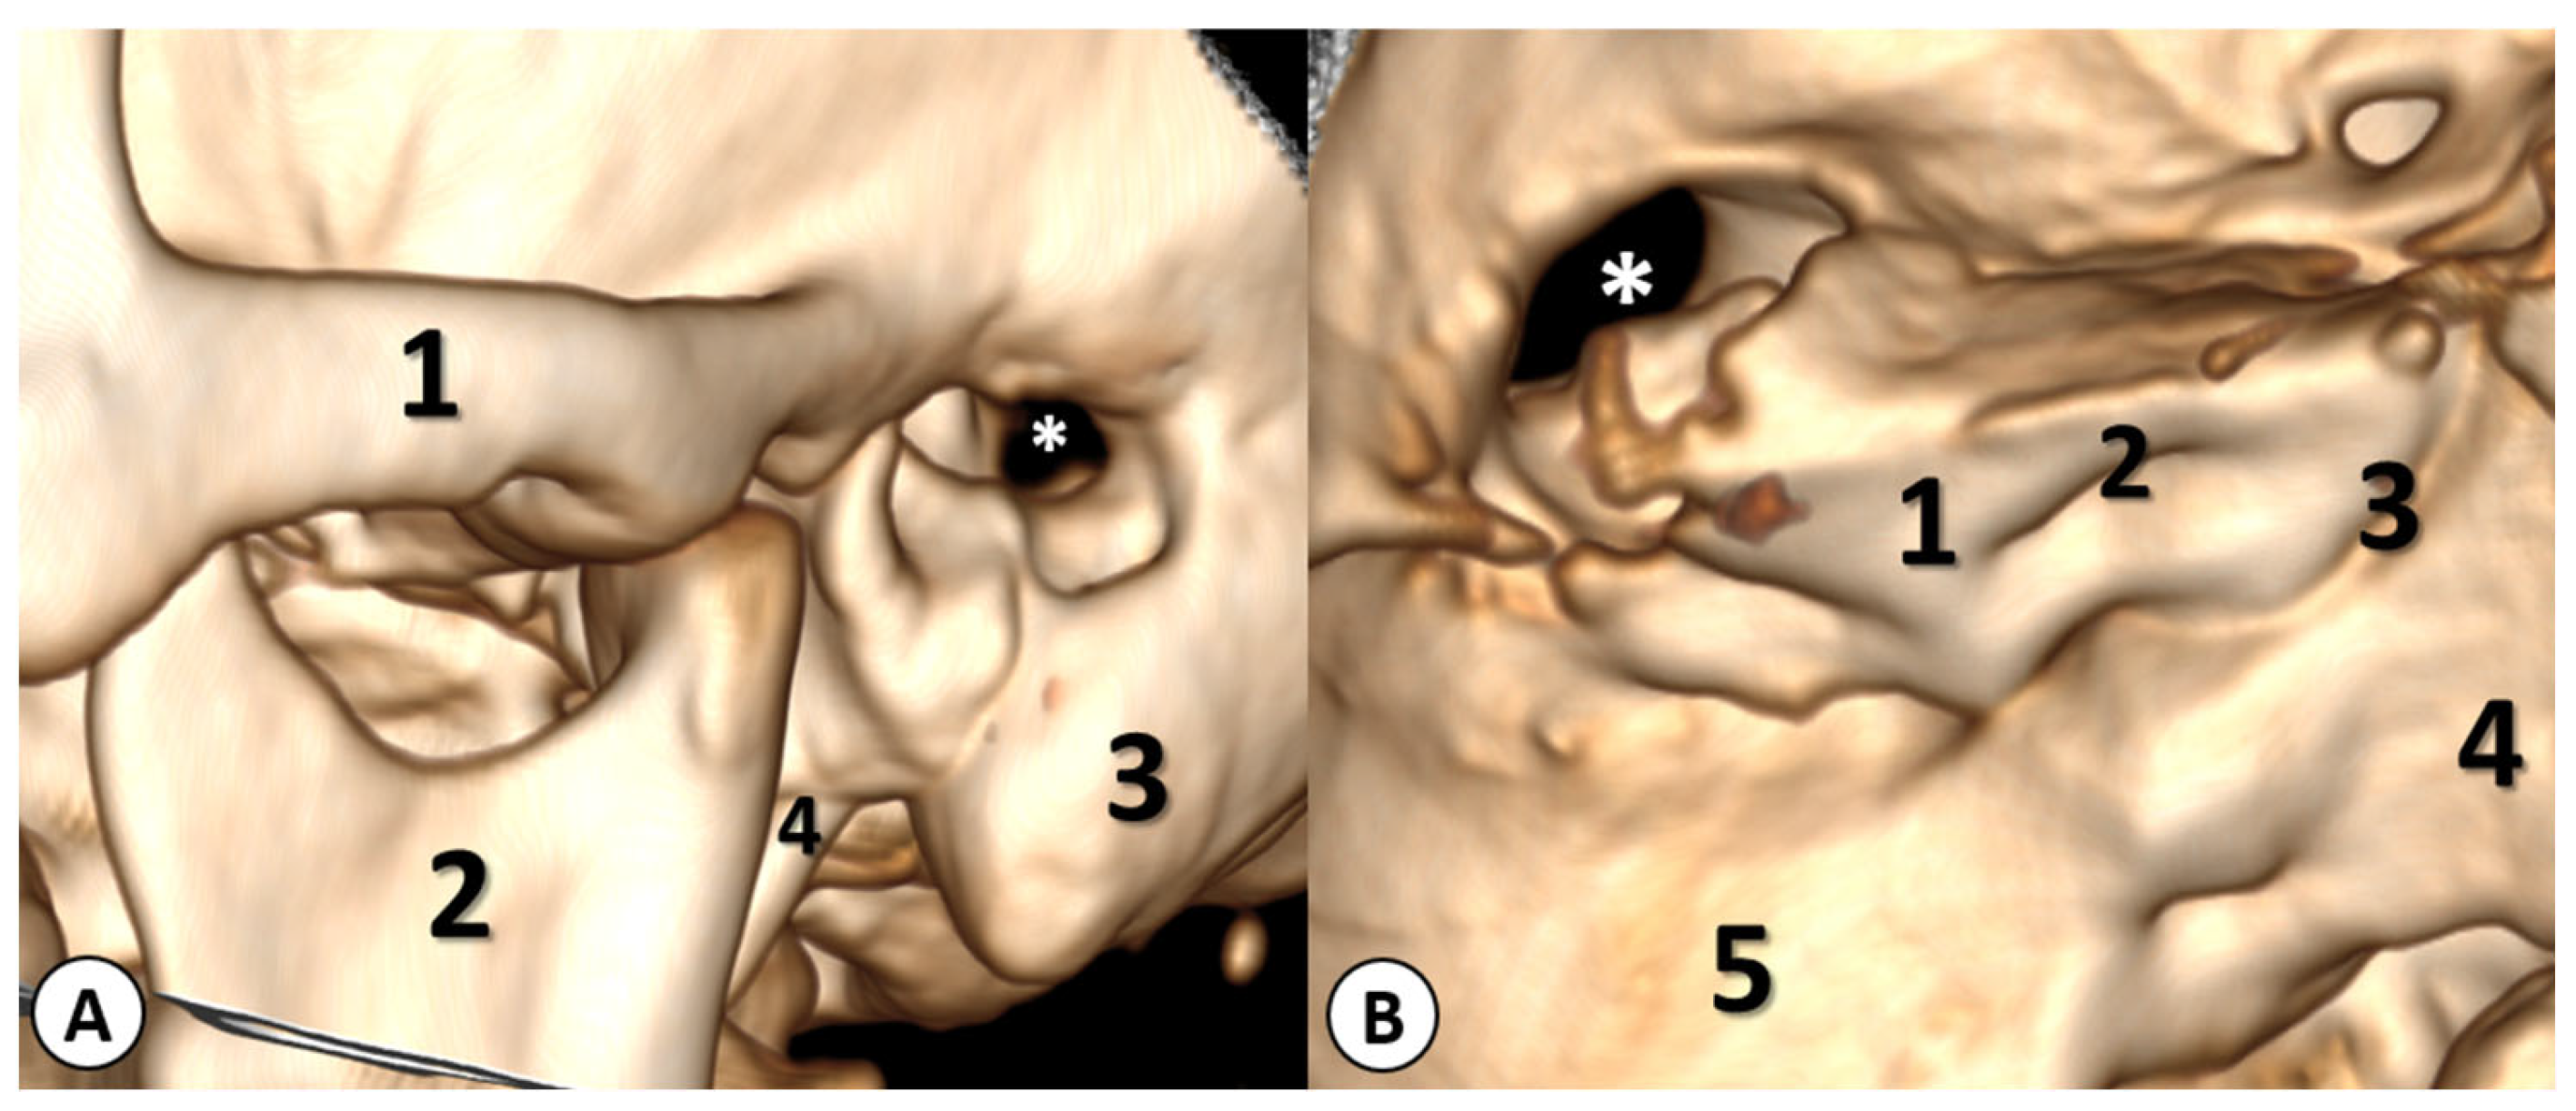

2.2.2. Imaging Studies

3.5. Imaging Studies